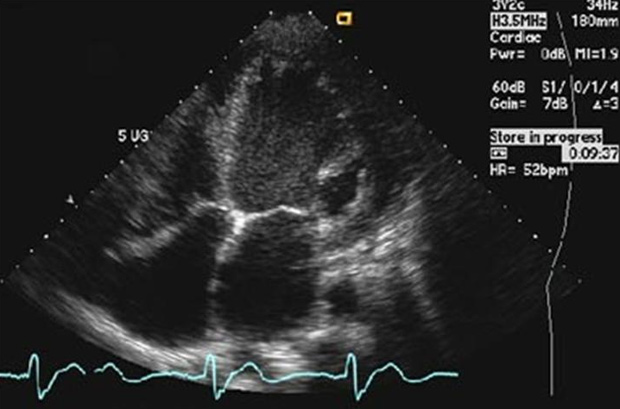

Cada coração tem sua cadência, mas alterações bruscas podem levar à morte

Uma frequência cardíaca muito baixa faz com que menos oxigênio circule pelo corpo. Com você deitado e quieto, ou mesmo dormindo, é provável que não haja nenhum problema se seu coração estiver com apenas 30 bpm. Mas essa frequência com você desperto, em pé, pode provocar desmaios e, em casos extremos, levar à morte.

Para um jovem saudável, a frequência normal fica entre 60 e 90 bpm. Mas um atleta, por exemplo, pode ter uma frequência de 40 bpm e isso ser absolutamente normal. É que o coração dele é muito eficiente: cada bombeada entrega ao corpo bem mais sangue que o normal, por isso ele precisa bater menos vezes.

O coração tem dois movimentos: a diástole (quando o órgão se enche de sangue) e a sístole (quando o sangue é bombeado para o corpo). Quando o coração acelera, ele encurta a diástole. Assim, o órgão envia menos sangue para o corpo, causando cansaço e desmaios. Uma frequência cardíaca perto dos 180 bpm é sinal de alerta total e perigo de morte.